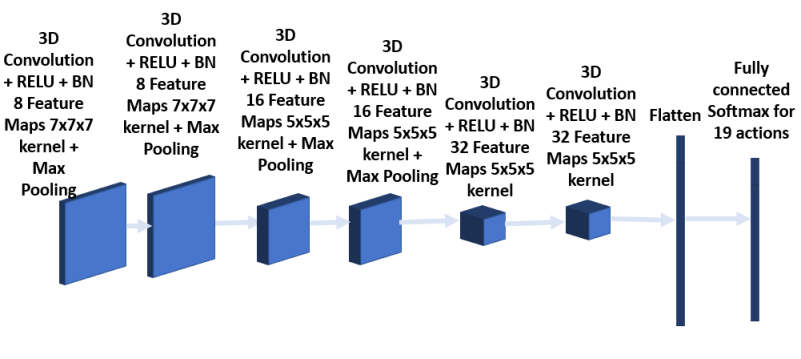

To improve overall performance, two other CNN architectures were trained besides the one described above, and the predicted bounding boxes using all three models are provided to the next stage for analysis. The architecture of the second model consists of 6 convolution layers as shown in Figures 7 and 8 respectively. The first 2 layers have kernel size 7x7x7, followed by 2 convolution layers with kernel size 5x5x5 and the final 2 convolution layers having kernel size 3x3x3. Each convolution layer is followed by batch normalization. Max pooling is added after the second and fourth layer. The third model as shown in Figures 9 and 10 has a convolution layer with 9x9x9 kernel and a batch normalization preceding the architecture in the model shown in Figures 5 and 6.